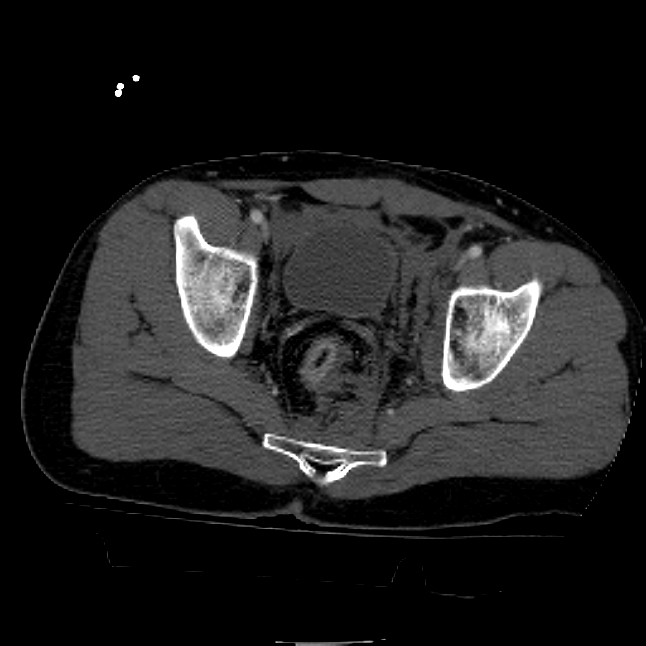

25 yo brittle diabetic, became hypoglycemic and passed out on his motorcycle. Sustained bilateral lateral Hoffa fractures with associated LCL injury on the right and right distal radius fracture. I have questions regarding his pelvic ring/acetabular fracture on the left. Appears to be a very low posterior column fracture with associated posterior wall, marginal impaction. Superior and inferior rami fractures as well on the left giving him a floating segment of inf ramus/ischium/posterior column, but no detectable posterior ring injury. Should the posterior column/posterior wall fracture be addressed surgically because of the marginal impaction? Or is this fracture low enough to be treated non-operatively? I appreciate the input.

It's an interesting case. The plain films show the impaction, but most of the joint looks pretty good. The CT cuts look awful, though.

The impaction is so big I don't think I would ignore it. It IS down low, but it takes up almost the whole southern hemisphere of his joint.